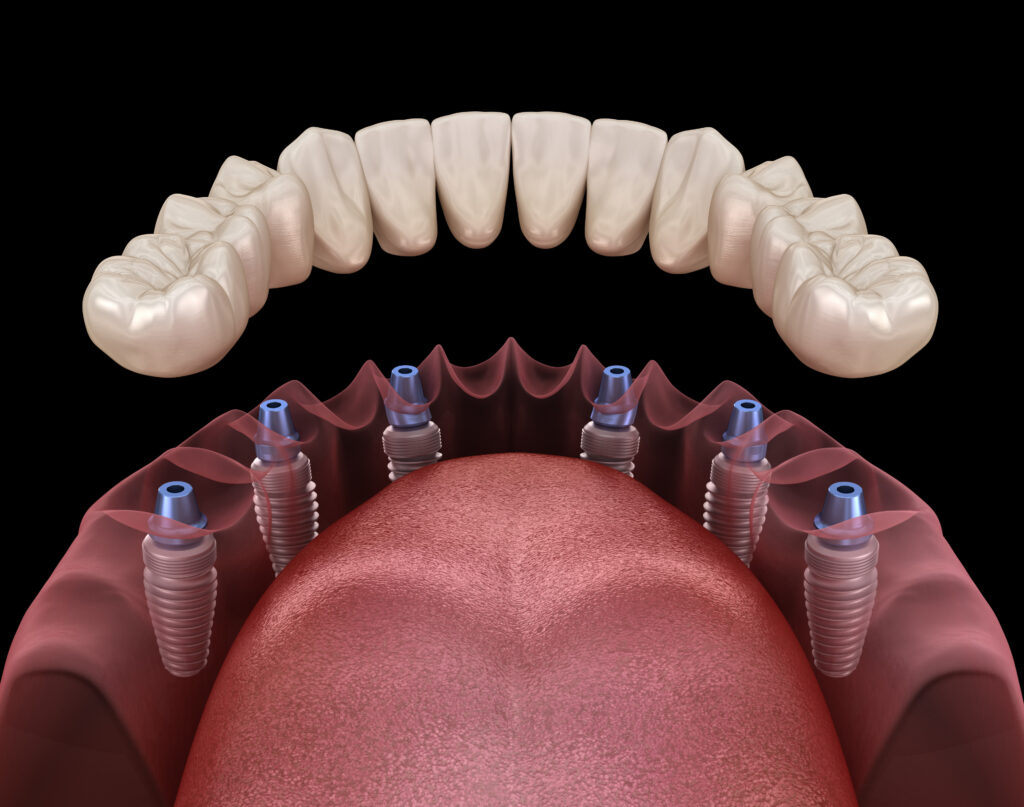

이러한 회기역치과 전체임플란트는

단순히 여러 개의 인공치를 심는 것이 아니라

턱뼈의 상태, 잇몸 두께, 교합 상태, 전신 건강을

종합적으로 고려해야 하는 복합 치료 방법입니다.

회기역치과 전체임플란트는 턱뼈에 단단히

고정되기 때문에 자연치와 유사한 저작력과

발음이 가능하고 음식의 맛도 온전히

느낄 수 있습니다.